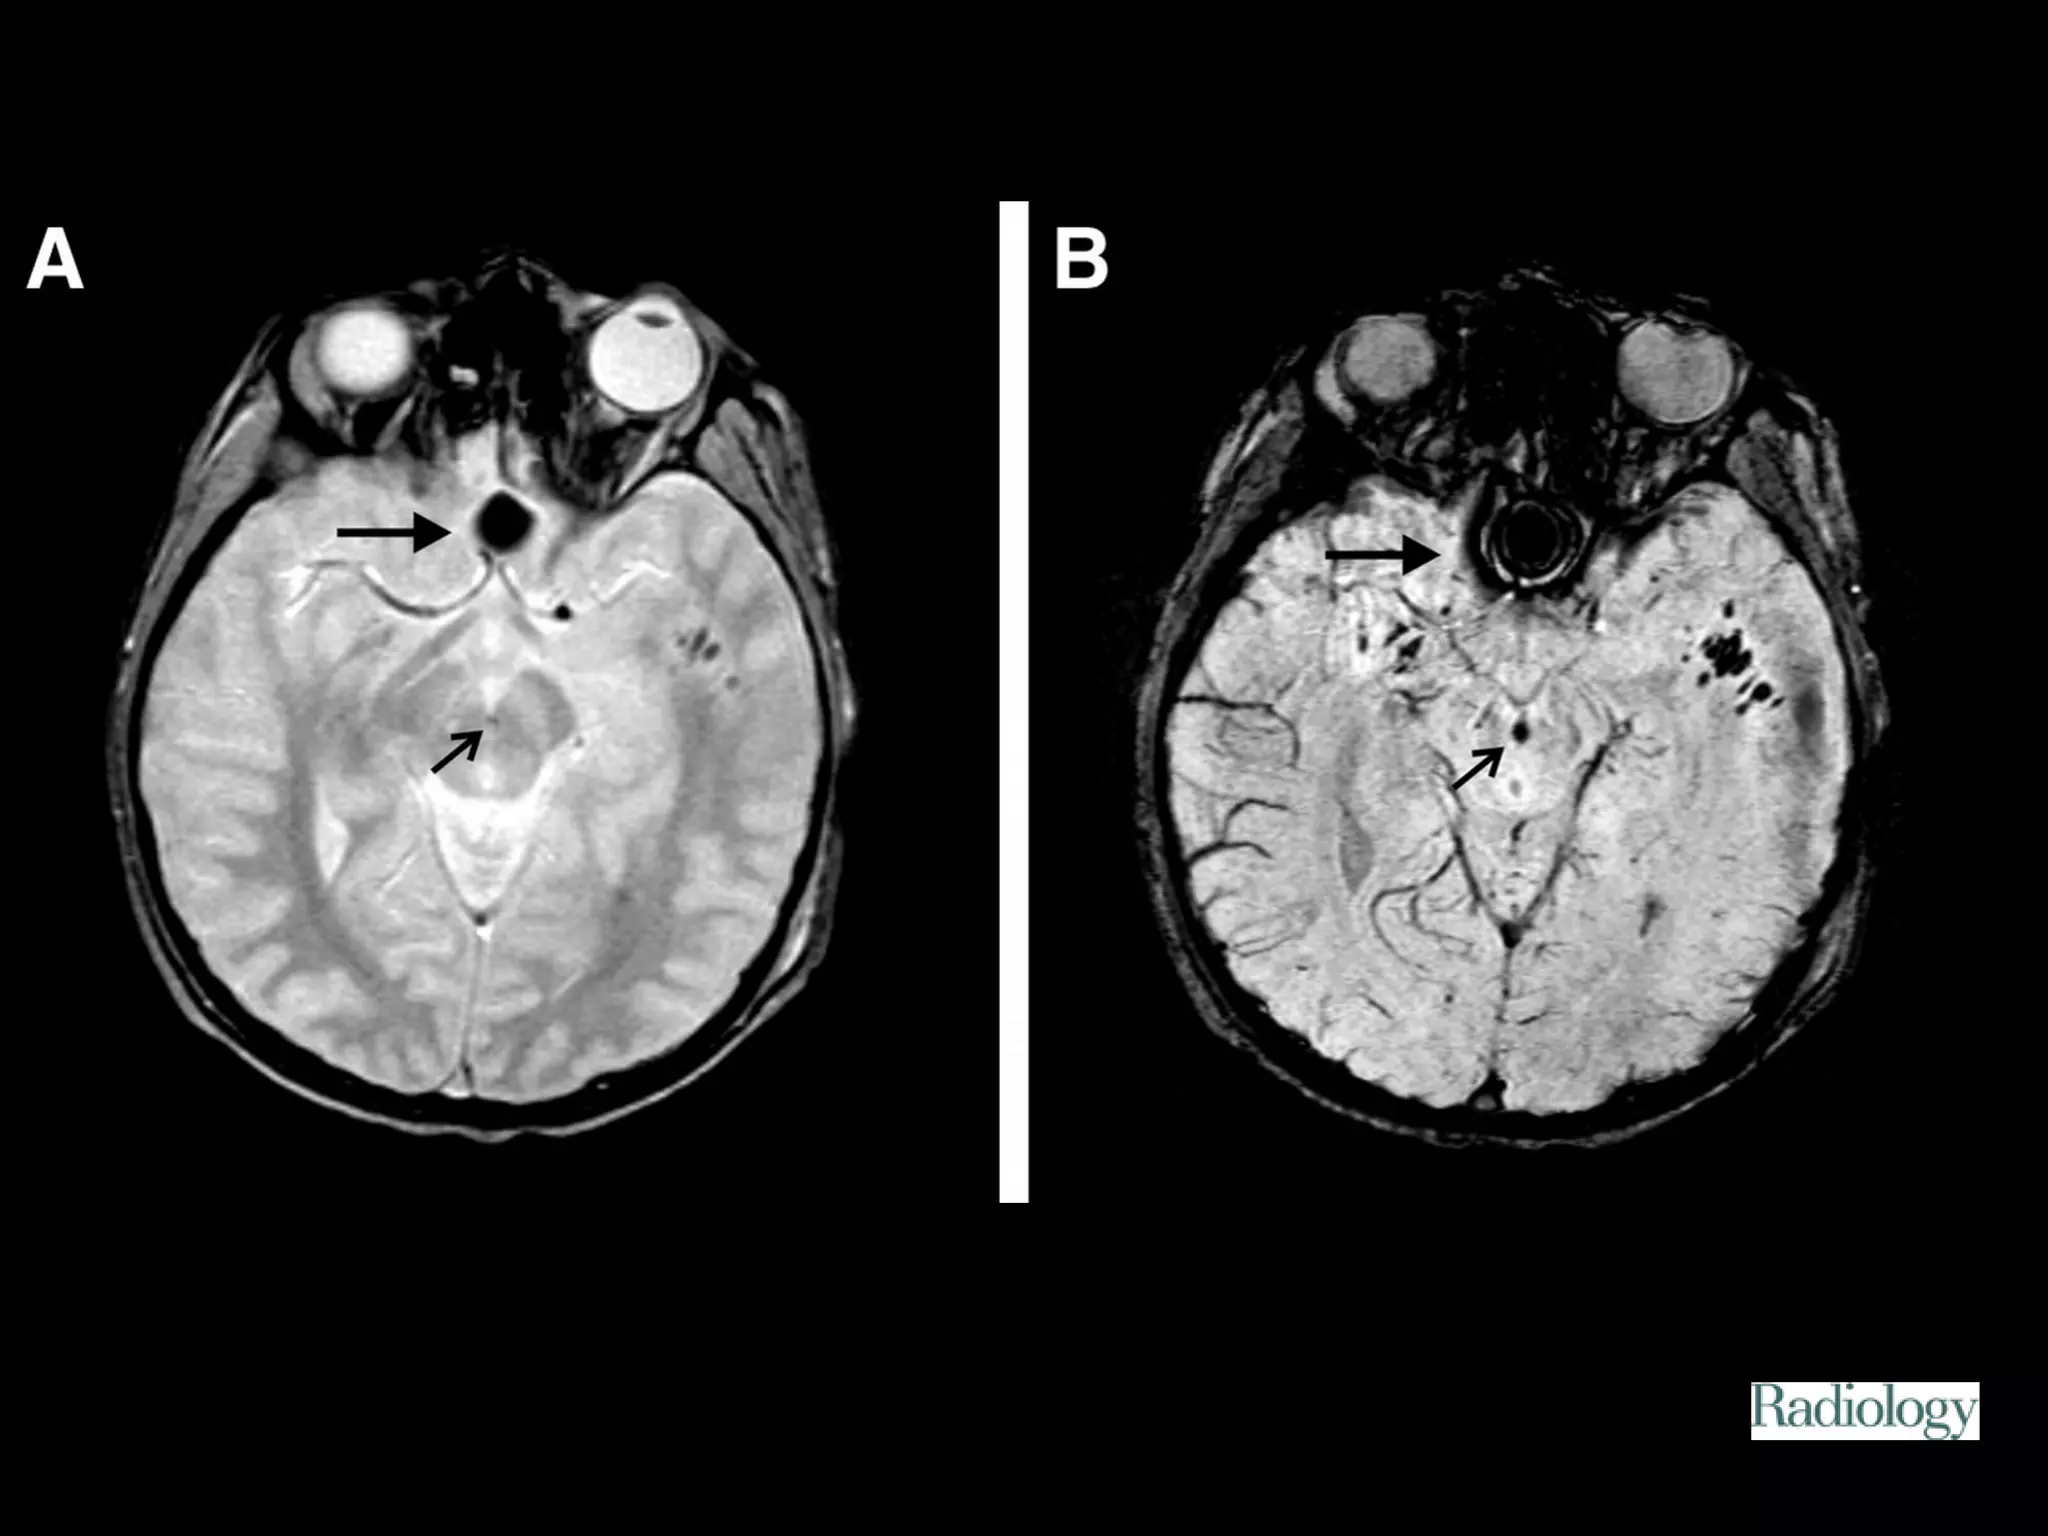

Diffuse axonal injury

Diffuse axonal injury (DAI) is a major form of traumatic

brain injury and is caused by shearing stress primarily in

white matter). Various outcomes are reported (ie, learning

disorders, moderate to severe disability, and vegetative

state) but were unable to correlate the extents of early

injury with the prognoses.

Among patients eventually

proven to have DAI, 50-80%

demonstrate a normal CT scan

upon presentation. Delayed CT

scanning may be helpful in

demonstrating edema or

atrophy, which are later

findings. Small petechial

hemorrhages located at the

gray-white matter junction, as

well as in the corpus callosum

and brainstem, are

characteristic of CT-scan

findings in the acute setting.

The ability to detect DAI by using imaging, whether

the lesions are hemorrhagic or nonhemorrhagic, has

substantially improved with the advent of MRI. MR

imaging has been helpful in defining patterns of

injury in adults with DAI—depicting involvement

predominantly in the frontal white matter, corpus

callosum, brainstem, and diencephalon.

Figure 1. Patient 2.

Tong K A et al. Radiology 2003;227:332-339

©2003 by Radiological Society of North America

Figure 2. Patient 4.